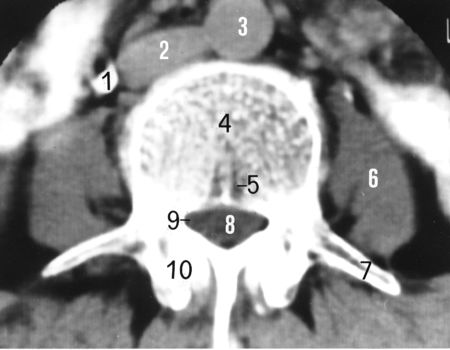

一、椎管的应用解剖

前壁:椎体、纤维环、后纵韧带。

后壁:椎弓和黄韧带。

两侧:椎弓根、上下关节突及关节囊,并以椎间孔向外开放。

黄韧带:起于上位椎管的下前缘,止于下位椎管的上后缘。

中央椎管:各腰椎椎孔形状,腰1、2多呈卵圆形,腰3、4多呈三角形,腰5多呈三叶形,其他尚可呈钟形、或橄榄形。因退变或其他病变、椎孔形状还可有不同改变。腰椎椎管自腰1、2间隙以下包含马尾神根.其被硬脊膜包围的部分形成硬膜囊,各种经根自硬膜囊发出后在椎管内的一段称为神经根管,以后分别自相应椎间孔穿出。

腰神经通道:腰神经根自硬脊膜囊发出后,经过较窄的骨纤维性管道,由椎间管穿出的径路统称为腰神经通道。此通道分为两段,第一段为神经根管,从硬膜囊穿出点至椎间管内口,第2段为椎间管

盘黄间隙:即椎间盘与黄韧带之间的间隙。

侧隐窝:侧隐窝位于侧椎管,也是神经根管的狭窄部分。

正常椎管

矢径(前后径):13~15mm。

横径(弓根间径):19~29mm (平均24mm)。

临床以矢径确定椎管狭窄

矢径 ‹ 13mm。

横径 ‹ 18mm。

矢径 ‹ 10mm为绝对狭窄。

L1~2(圆形)

L3~4(三角形)

L5(三叶形)